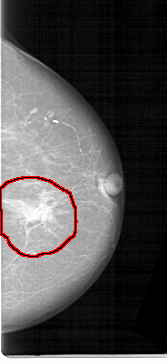

D_4184_1.RIGHT_MLO

FILE: D_4184_1.LEFT_MLO.OVERLAY

TOTAL_ABNORMALITIES 1

ABNORMALITY 1

LESION_TYPE MASS SHAPE IRREGULAR MARGINS ILL_DEFINED

ASSESSMENT 3

SUBTLETY 5

PATHOLOGY MALIGNANT

TOTAL_OUTLINES 1

BOUNDARY